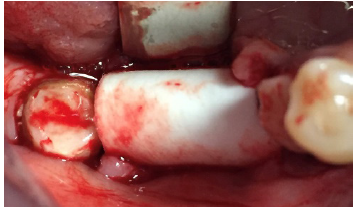

buccal and lingual flaps were elevated to expose the very narrow edentulous ridge (Figure

4). With the aid of a sharp piezo-surgical tip the narrow ridge was perforated in the buccal

aspect to promote some bleeding from the marrow spaces and in order to hydrate the bone

graft placed to its buccal aspect. It was a mix of autogenous bone scarped from the area and

collagenated porcine bone (GenOs, Tecnoss, Coazze, TO, Italy), the newly shaped ridge (Figure

5) was than covered with a curved cortical lamina, cut and shaped in order to fit the area and

protect the underlying grafted ridge (Figure 6).

Figure 4: Extremely resorbed ridge.

Figure 5: Aspect of the grafted ridge.

Figure 6: application of cortical lamina.